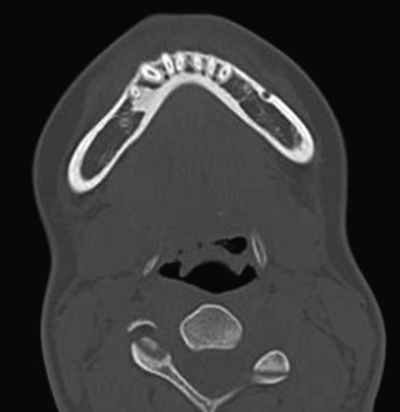

15歳の男子。かかりつけ歯科医のエックス線検査で右側の下顎小臼歯部に異常を指摘され、精査を希望して来院した。自覚症状はないという。初診時のエックス線写真とCTを別に示す。

疑われるのはどれか。1つ選べ。